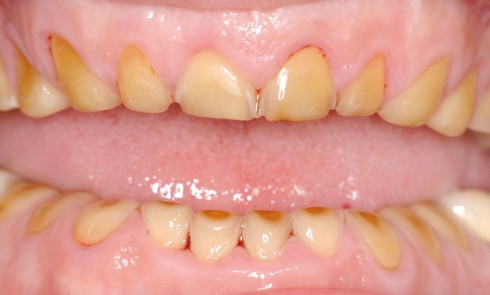

Article réservé à nos abonnés Érosions dentaires : stratégie et étapes de réhabilitation prothétique

L’usure dentaire est de plus en plus fréquente au sein de nos cabinets. Nos patients y sont sujets de par...

Article réservé à nos abonnés Destructions amélo-dentinaires sévères et reconstruction globale céramique sans temporisation

L’origine des pertes de substance dentaire sous l’effet de phénomènes d’usure et d’érosion, donc hors traumatologie et processus carieux, est...